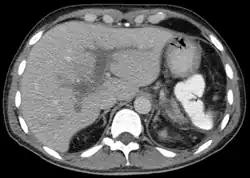

Portal vein thrombosis seen with computed tomography. | |

The diagnosis of portal vein thrombosis is usually made with imaging confirming a clot in the portal vein; ultrasound is the least invasive method and the addition of the Doppler technique shows a filling defect in blood flow. PVT may be classified as either occlusive or nonocclusive based on evidence of blood flow around the clot.[5] An alternative characterization based on site can be made: Type 1 is limited to the main portal vein, Type 2 involves only a portal vein branch (2a, or 2b if both branches are affected), and Type 3 if clot is found throughout both areas.[8] Determination of condition severity may be derived via computed tomography (CT) with contrast, magnetic resonance imaging (MRI), or MR angiography (MRA). Those with chronic PVT may undergo upper endoscopy (esophagogastroduodenoscopy, EGD) to evaluate the presence of concurrent dilated veins (varices) in the stomach or esophagus.[3] Other than perhaps slightly elevated transaminases, laboratory tests to evaluate liver function are typically normal.[1] D-dimer levels in the blood may be elevated as a result of fibrin breakdown.